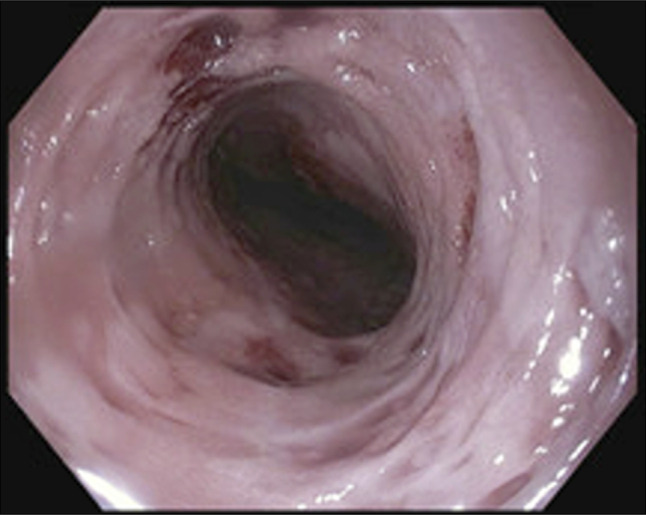

摘要食管壁内假性憩室病(EIPD)是一种罕见的疾病,在内镜下表现为食管壁内有许多小的流出物。虽然通常与吞咽困难等良性症状相关,但EIPD与食管恶性肿瘤有关,既是一种易感疾病,也是相关的共存诊断。然而,两者之间的联系尚不清楚。本病例报告详细介绍了一名有EIPD病史的患者,在整个食管高度发育不良的情况下发展为多灶性浅表鳞状细胞癌。

Esophageal intramural pseudodiverticulosis (EIPD) is a rare disease characterized endoscopically by numerous small outpouchings within the esophageal wall. While typically associated with benign symptoms such as dysphagia, EIPD has been linked to esophageal malignancy, both as a predisposing condition and associated coexisting diagnosis. However, the association is not clear. This case report details a patient with a history of EIPD who developed multifocal superficial squamous cell carcinoma in the context of high-grade dysplasia throughout the esophagus.